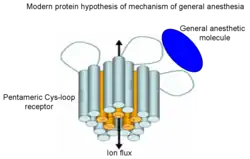

However, the proteins considered the most likely molecular targets of anaesthetics are ion channels. According to this theory general anaesthetics are much more selective than in the frame of lipid hypothesis and they bind directly only to small number of targets in the central nervous system mostly ligand-gated ion channels in synapses and G-protein coupled receptors altering their ion flux. Particularly Cys-loop receptors[42] are plausible targets for general anaesthetics that bind at the interface between the subunits. The Cys-loop receptor superfamily includes inhibitory receptors (GABAA receptors, GABAC receptors, glycine receptors) and excitatory receptors (nicotinic acetylcholine receptor and 5-HT3 serotonin receptor). General anaesthetics can inhibit the channel functions of excitatory receptors or potentiate functions of inhibitory receptors, respectively.

A number of experimental and computational studies have shown that general anaesthetics could alter the dynamics in the flexible loops that connect α-helices in a bundle and are exposed to the membrane-water interface of Cys-loop receptors.[43][44][45][46][47][48] The main binding pockets of general anaesthetics, however, are located within transmembrane four-α-helix bundles of Cys-loop receptors.[49][50][51]